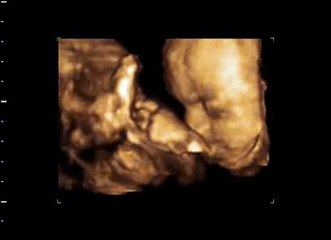

3D Ultraschall 31 ssw